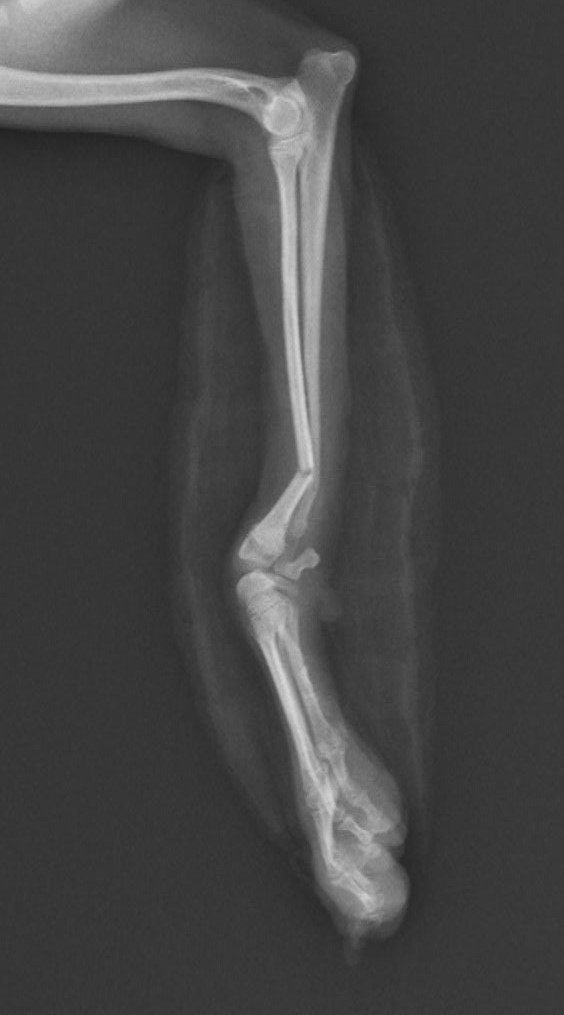

右前腕骨折のポメラニアンちゃんが来院されました。橈尺骨骨折は動物病院では一番よくある骨折です。ロッキングプレートであるTAITAN1.2で対応しました。治りも順調で元気に帰りました。よかったね。